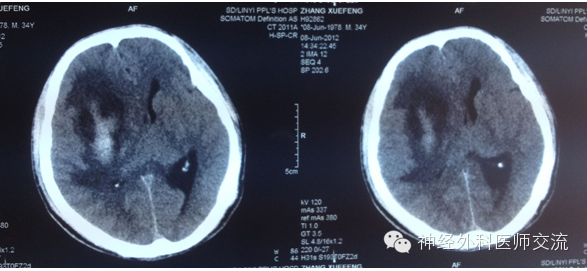

(2)CT图片处理——穿刺点的选择及介入手术入路

① 确定穿刺平面:据CT所显示的血肿,选择血肿最大断层,即为要穿刺的平面,也就是说:操作时要将引流导管沿着这一血肿最大层面进入血肿腔内。确定该层面至颅底层面的距离(即厚度)(X毫米:一般为50~60 mm)。

② 确定穿刺点:在血肿的最大层面上划出血肿的最大长轴线,与前额头皮的交点即为理论穿刺点,测出该点至血肿远端的距离(毫米),该数值减去5mm~10mm即为置管深度,一般为80~120mm。

确定实际穿刺点要做到两个避开:避开额窦、避开上矢状窦!实际穿刺点,一般为正中矢状线旁开15mm~20mm,内眦上方45mm~60mm的前额之交点,多为55mm。

置入引流导管之概要:

1.确定穿刺点,但过一点可做无数条射(直)线;

2.确定穿刺平面,即血肿的最大CT段层面,再将经过穿刺点的射线,局限在穿刺平面内;

3.确定最优路径,在穿刺平面内选择经过穿刺点,且基本为血肿最大长轴线的那条射线。

具体操作时,就是将引流导管经过穿刺点的骨孔,沿着该条假设的射线进入血肿腔的远端。